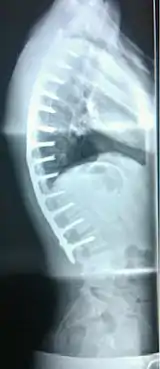

| Scheuermann's disease on lateral Xray of the T spine | |